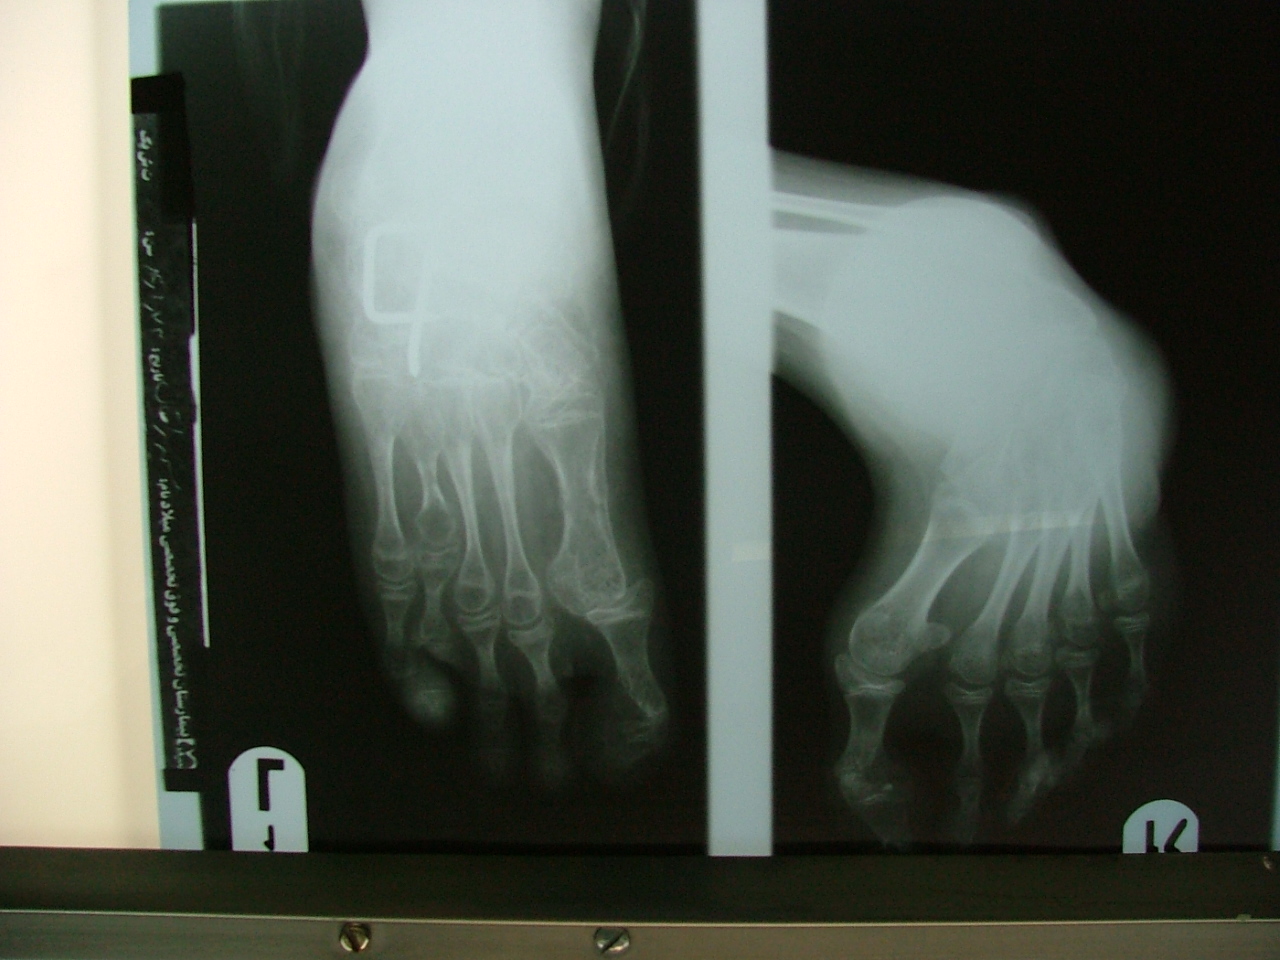

تهیه و تامین تجهیزات ارتوپدی و مشارکت در انجام اعمال جراحی ارتوپدی و عمل‌های نادر عضو تیم جراحی افزایش قد -جهت ترمیم شکستگی های قدیمی و جوش نخورده گی ها -طویل کردن اندامها- طویل کردن انگشت قطع شده - تعویض مفصل لگن _تعویض مفصل زانو _ بازسازی رباطACLوPCL_اصلاح ناهنجاریهای مادر زادی -با همکاری پزشکان و متخصصان مجرب آموزش دیده در روسیه و اتریش و سوئیس بروش جراحی ایلیزاروف و lon و lsa و واگنر و اسلایدینگ نیز جدید ترین روش افزایش قد و اندام در سال 1397 بنام hil هیل برای اولین بار- افزایش قد به 6 روش جراحی و جدیدترین روش در اروپا و روسیه. آدرس مطب _تهرانسر بلوار اصلی مجتمع سهند طبقه4 واحد 410

تهیه و تامین تجهیزات  ومشارکت در انجام اعمال جراحی  ارتوپدی

-جهت ترمیم شکستگی های قدیمی و جوش نخورده گی ها -

طویل کردن اندامها- طویل کردن انگشت

-اصلاح ناهنجاریهای مادر زادی

باهمکاری پزشکان و متخصصان مجرب بروش جراحی ایلیزاروف